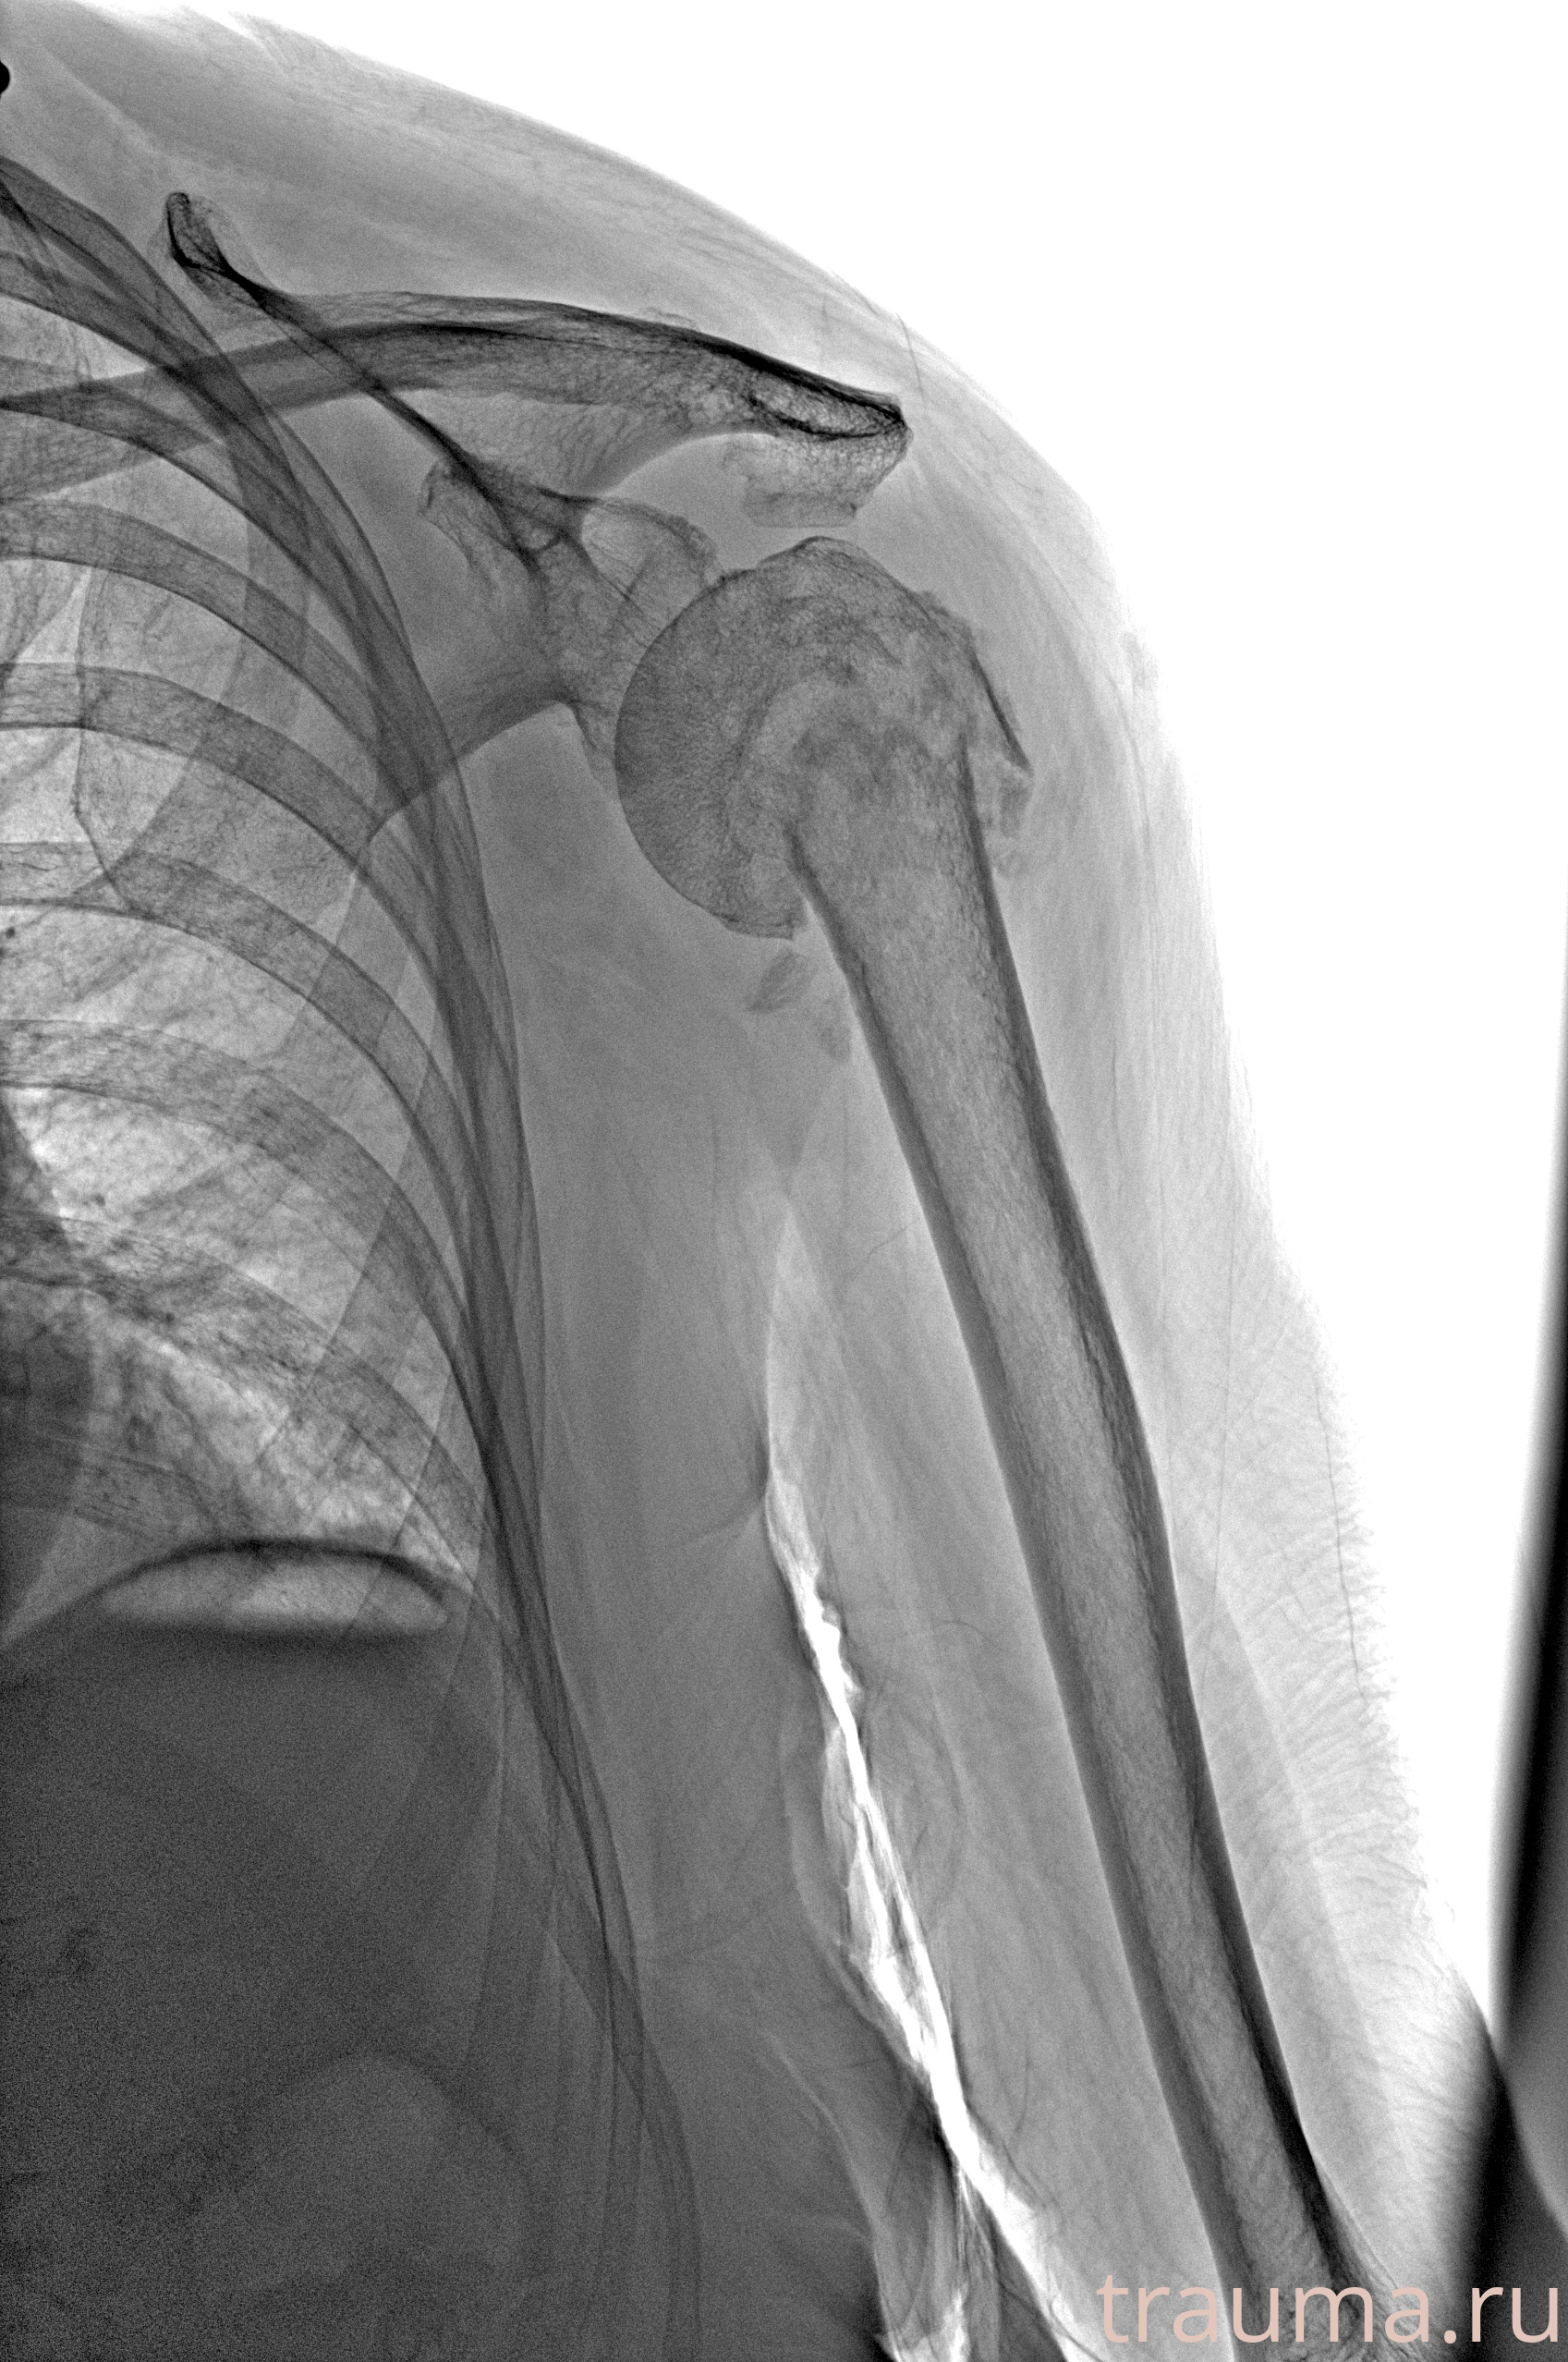

Рентгенограммы

Рентген на дому: по вашему адресу приезжает врач-рентгенолог, травматолог-ортопед с мобильным рентгеновским аппаратом, проводит диагностику травмы или заболевания, делает необходимые рентгенограммы, дает рекомендации по дальнейшему лечению. Получить качественные снимки в домашних условиях возможно благодаря уникальной методике, разработанной МосРентген Центром для института  Склифосовского